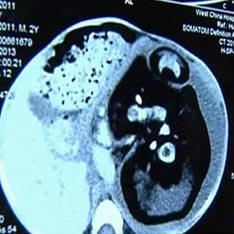

Kirurgi so njegovega nerojenega našli v želodcu dveletnega otroka Siamski dvojček. Z nenavadnim primerom v svoji praksi soočeni z zdravniki s Kitajske. Po pregledu zdravniki dveletni fant z ogromnim trebuhom iz Huashi Villagea, izkazalo se je, da je bil v njem njegov nerojeni brat dvojček. Odločeni so bili za nujno operacijo, saj je želodec otekel neverjetne velikosti, začeli so se srkati notranji organi in dojenčku je postalo težko dihati, piše Daily Mail. Izkazalo se je, da je brat, ki je bil ves ta čas v njem, ni bilo veliko manjši od samega fanta. Njegovo telo je bilo nerazvito, hrbtenica oz. okončine in prsti na rokah in nogah so v celoti oblikovani. Tale primer, so pojasnili zdravniki, je ena od sort siamske dvojčka. Rodijo se, ko je oplojeno jajčece ni v celoti deljeno. Ampak, kot je opozoril neonatolog iz vrtca Jonathan Fanarof, bolnišnica v Clevelandu, v primeru “noseč” dojenček, jajce ni delilo.

V celotni zgodovini medicine je na stotine primerov, ko je eden dvojčka zarodkov brat absorbira in nadaljuje razvoj znotraj njega. Ta pojav se vedno pojavi zgodaj. stopnje nosečnosti in običajno oba ploda umreta v maternici matere. Zgodi pa se, da je porod uspešen in ujet zarodek pasti še naprej živi kot parazit, povezan z njim večji brat nekakšna popkovina. Na koncu še on postane tako velik, da začne škodovati sebi lastniku. V medicini se ta anomalija imenuje plod v plodu (zarodek v zarodku). Mimogrede, zabeležen je bil isti primer pred nekaj leti v Indiji. Trebuh 36-letne Sanju Bhagat je bil toliko napihnil, da je bil videti kot ženska, ki se bo kmalu bo rodila. Kirurgi so bili prepričani, da ima ogromen tumor, ki pritiska na diafragmo. Toda kakšno je bilo njihovo presenečenje, ko ga ni bilo vzeli so mu maternico mutiranega telesa njegovega brata dvojčka.